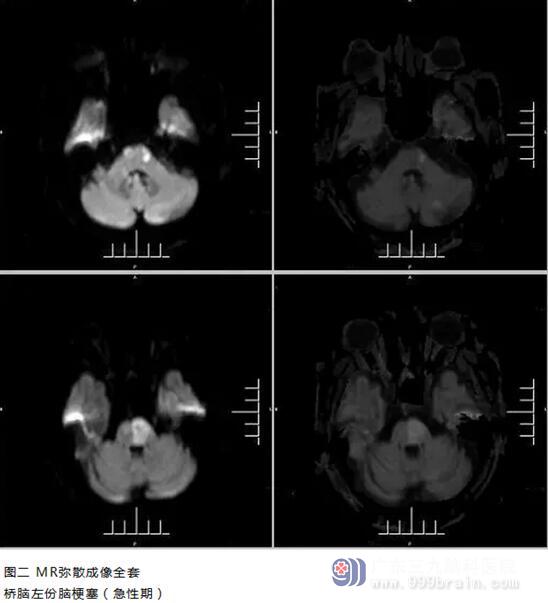

到医院后,神经内一科立即为李老先生开通绿色通道,在完善心电图、CT血管成像、MR弥散成像全套等检查后,发现李老先生基底动脉中远段显影中断,桥脑左份脑梗死,考虑为急性闭塞。经过慎重评估,在取得家属同意的情况下,决定进行动脉内机械取栓血管再通术。